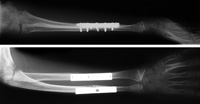

In these x-rays, fractures in both the radius and the ulna have been repaired with plates and screws.

Reproduced from Pring M, Chambers H: Pediatric forearm fractures. Orthopaedic Knowledge Online Journal 2007; 5(5). Accessed October 2014.

During surgery, your doctor will open the skin and reposition the broken bone fragments (a procedure called an open reduction). Your doctor may use pins, metal implants, or a cast to hold the broken bones in place until they have healed.